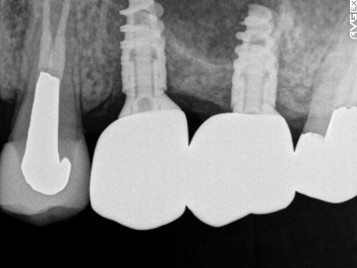

右上の犬歯と小臼歯の2本が、歯根の破折を起こしていましたので、抜歯しました。抜歯後インプラントを1本埋入し、以前(2013年1月)5本埋入していたインプラントを活用して被せ物を新しくしました。

所感

2013年1月にインプラント治療をした5本を活用し、今回新たに1本埋入したインプラントと合計6本を連結し、新しい被せ物にしました。

Before

歯根破折を起こしていたため2本抜歯しました。

【抜歯後】

After

インプラントを新たに1本埋入しました。